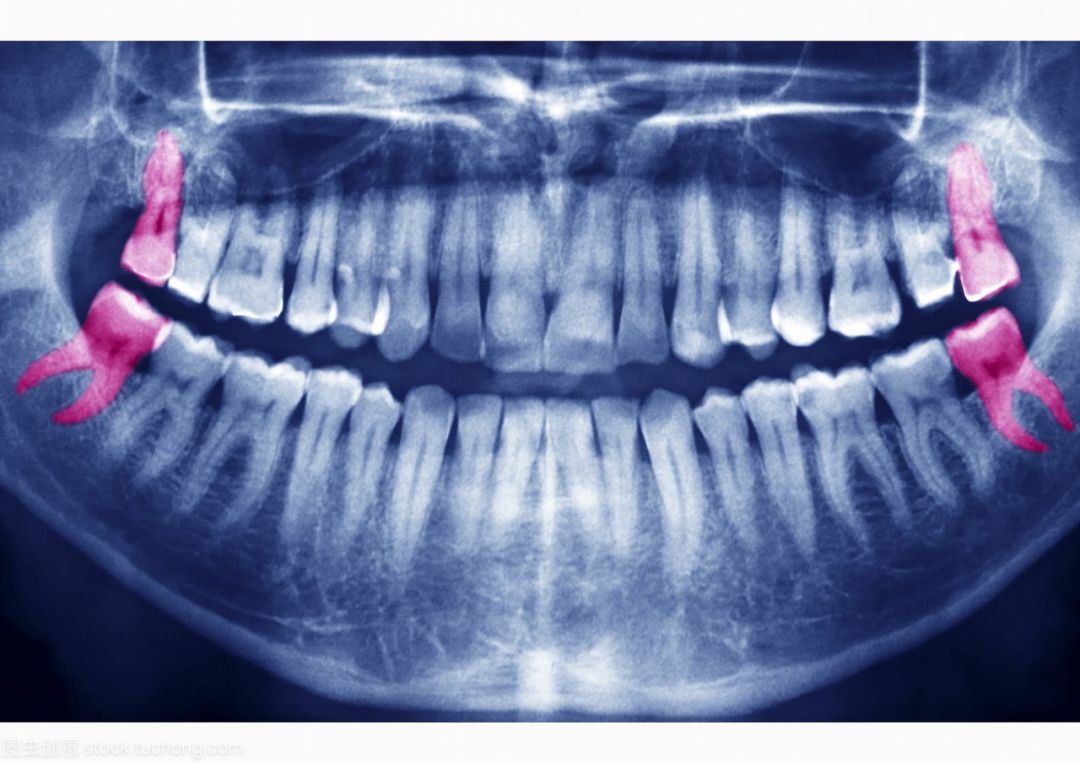

大部分人智齿都这样长

各种奇形怪状

自己不好好长就算了,还会骚扰隔壁邻居

这种智齿必须要拔掉!!!